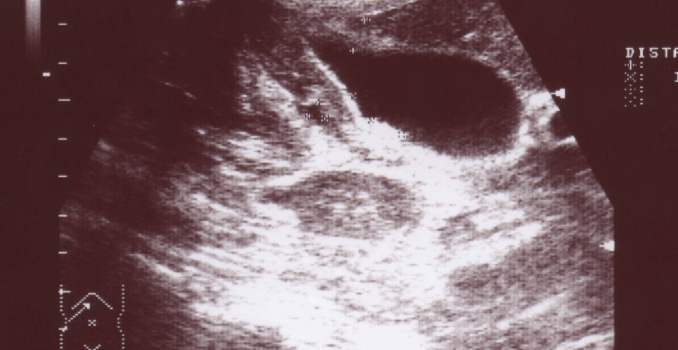

При проведении ультразвукового исследования (УЗИ) можно обнаружить характерные признаки цирроза печени:

- Размеры печени увеличены, особенно левая доля (на ранних стадиях заболевания), в то время как правая доля уменьшена.

- В стадии декомпенсации цирроза наблюдается уменьшение размеров органа.

- Нижний край печени имеет закругленную форму.

- Внешние контуры органа неровные.

- Структура печени неоднородная из-за наличия узлов регенерации.

- Эхоструктура печени повышена из-за замещения нормальной ткани соединительной и развития жировой инфильтрации (это наблюдается на ранних стадиях цирроза).

- Эхогенность печени снижена (это можно увидеть на последней стадии цирроза из-за атрофии органа, наличия узлов регенерации и фиброзной ткани).

Так выглядит цирроз печени.

Важно отметить, что цирроз печени проходит через несколько стадий, и каждая из них имеет свои особенности при ультразвуковом исследовании. На начальных стадиях заболевания в печени можно обнаружить отдельные крупные зоны повышенного эхосигнала, а структура селезенки будет однородной

Сформировавшийся цирроз печени выглядит как мозаичная картина, при этом меняется сосудистый рисунок. Мелкие вены воротной системы не видны, а воротная вена расширена и имеет более плотные стенки, чем обычно. На этом этапе можно наблюдать коллатеральное кровообращение в периферической зоне органа.

Также на УЗИ можно увидеть мелкоочаговые образования повышенной плотности в селезенке. Селезеночная вена будет расширена и извита в области ворот.

Для достоверного диагноза цирроза печени по данным УЗИ необходимо наличие трех прямых или двух прямых и двух косвенных признаков.